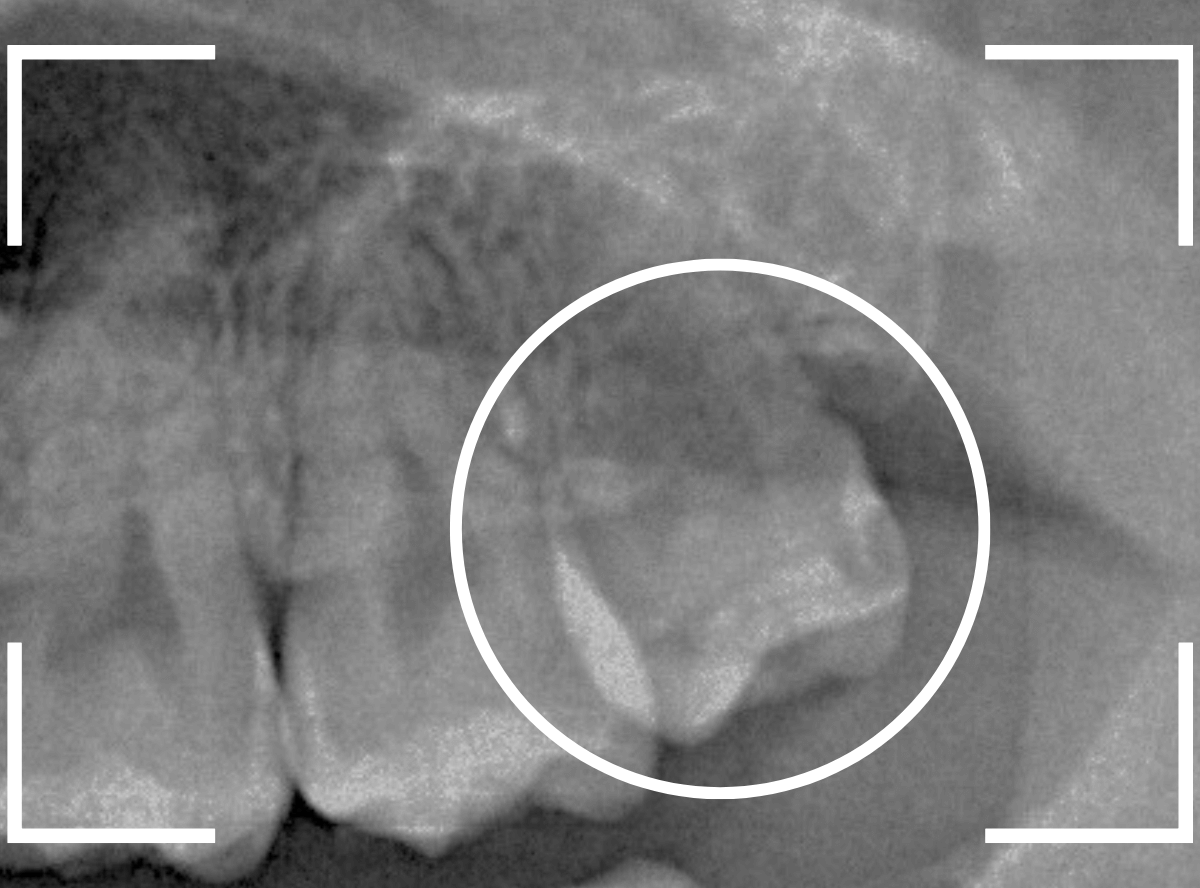

ここでは、比較的簡単なおやしらずの抜歯の例を中心にご紹介します。

このようなおやしらず、あなたはありませんか?